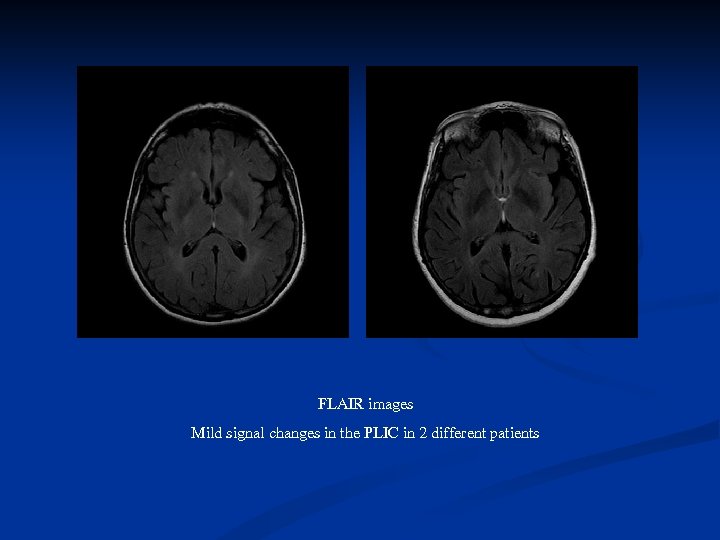

FLAIR images Mild signal changes in the PLIC in 2 different patients

FLAIR images Mild signal changes in the PLIC in 2 different patients